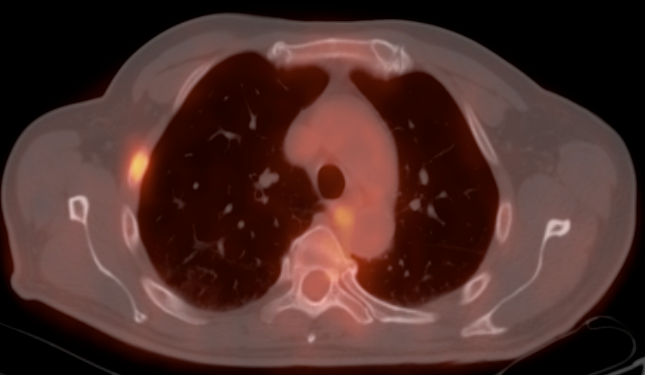

Metastases:

The most common sites of metastatic disease include the lymph nodes (regional & distant), liver, lung, peritoneal cavity, bones, brain and adrenal glands.